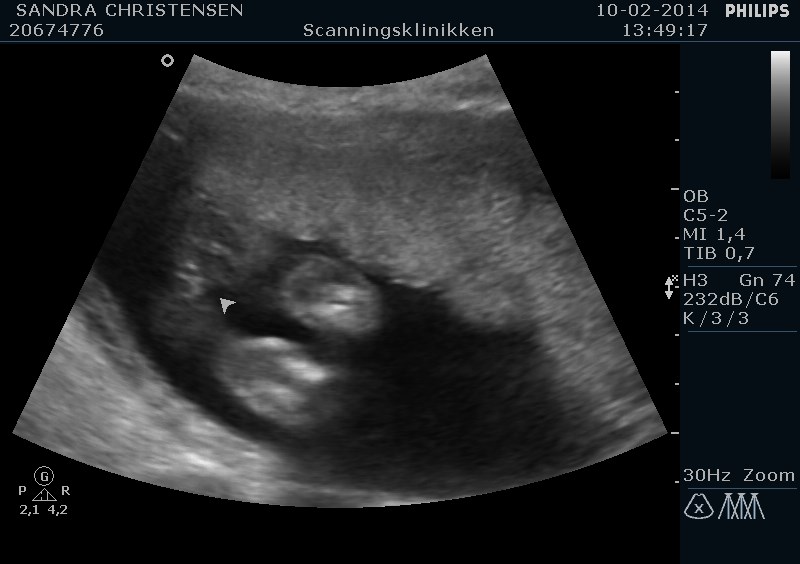

Hej

Er der nogen der ved noget om skannings billeder... Jeg er 14+ 3 og i dag har jeg været til kønskanning..

Der fik jeg taget et billed og der sagde hun ar det var en dreng.

Hvad synes I???